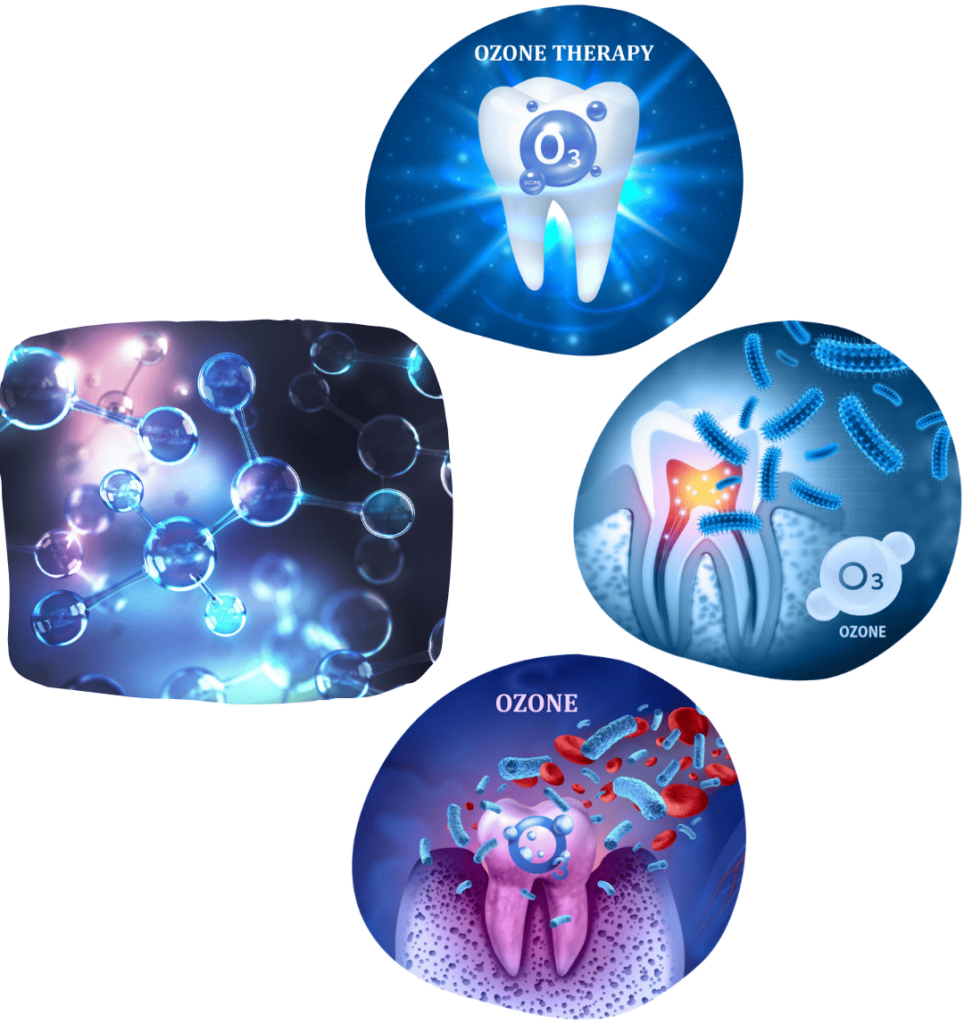

TOOTH EXTRACTION

Tooth extraction is the procedure of removing a tooth from the jaw. Although we always strive to preserve the natural tooth, in certain situations extraction is unavoidable.

The procedure is indicated in cases of severely damaged teeth, advanced periodontal disease, after trauma, or due to insufficient space for orthodontic treatment.

We perform extractions using minimally invasive techniques to preserve the surrounding tissue, ensuring that recovery is as comfortable and brief as possible.

The absence of a tooth compromises the stability of the remaining teeth, causing them to shift and rotate, changes in the bite, disorders of the jaw joint, and accelerated bone loss — all of which can limit the options available for optimal treatment.

That is why it is very important to replace an extracted tooth as soon as possible.

Teeth can be replaced with implants, crowns, bridges, dental prostheses, or a combination of prosthetic restorations.

The advantage of dental implants is that they do not require preparation of adjacent healthy teeth, fully replace the lost tooth, preserve surrounding teeth, and prevent bone loss.